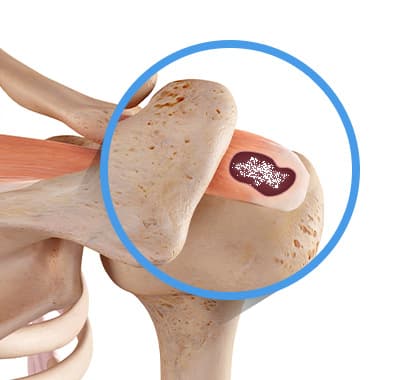

형성기 — 무른 석회

힘줄 내 석회가 갓 형성된 시기. 치약처럼 물렁물렁하며 비교적 제거가 쉽습니다.

휴지기 — 단단한 석회

분필처럼 굳어진 상태. 2세대 주사흡입술로는 제거가 어렵고, 3세대 분쇄흡입술이 필요합니다.

흡수기 — 액체화된 석회

석회가 녹아 액체화되는 시기. 극심한 통증이 동반되며 즉각적인 흡입 제거로 빠른 통증 완화가 가능합니다.

복합 파열 동반

석회성건염과 회전근개 파열이 함께 있는 경우. 석회 제거 후 인대 상태를 추가 평가하여 병합치료를 계획합니다.

석회성건염은 단순히 칼슘이 쌓이는 것이 아닙니다. 형성→휴지→흡수의 3단계를 거치며, 각 단계마다 통증 양상과 치료 방법이 달라집니다. 어느 단계인지 정확히 파악하는 것이 치료의 출발점입니다.

형성기 (Formative Phase)

통증 거의 없음힘줄 세포가 죽으면서 칼슘이 침착되기 시작하는 단계입니다. 석회가 아직 무르고 치약 같은 형태입니다.

이 단계에서는 충격파나 주사치료로도 효과가 있습니다.

휴지기 (Resting Phase)

간헐적 둔통석회가 굳어지는 단계입니다. 분필 같은 단단한 덩어리가 됩니다. X-ray에서 하얀 덩어리로 선명하게 보입니다.

단단한 석회는 주사흡입술(2세대)로 제거가 어렵습니다. 3세대 분쇄흡입술이 필요합니다.

흡수기 (Resorptive Phase)

극심한 통증 (야간에도)석회가 자연 흡수되려는 단계입니다. 혈관이 침입하면서 석회가 무너지는 과정에서 강렬한 염증 반응이 일어납니다.

흡수기에는 석회가 액체화되어 주사흡입술로도 제거가 가능합니다. 단, 극심한 통증 완화를 위해 즉시 시술이 필요합니다.